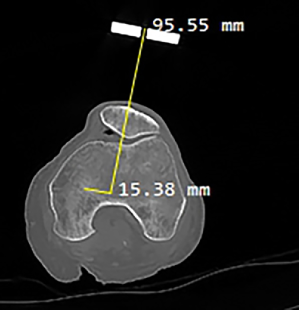

(b) CT Scan slice of femoral head, with measurements from the RB1.

IV-B Local Transformations

A CT scan of the leg is essential to determine the vectors for any point of the leg with respect to one of the marker frames. It is beneficial to perform the CT scan in various positions to enable measurements of different points of the leg as shown in Figure 5b, where the measurements was taken for the local translation from RB1 to the centre of the femoral head. Figure 7 shows a CT scan of the femur and the relationship between the mechanical and anatomical axes of rotation of the femur relative to the hip. Using dynamic frames on the leg, we can determine any positions on the leg or arthroscope at any point in time, and relative to a specific frame. For instance, point C (or vector from W to C) on the leg relative to W is: